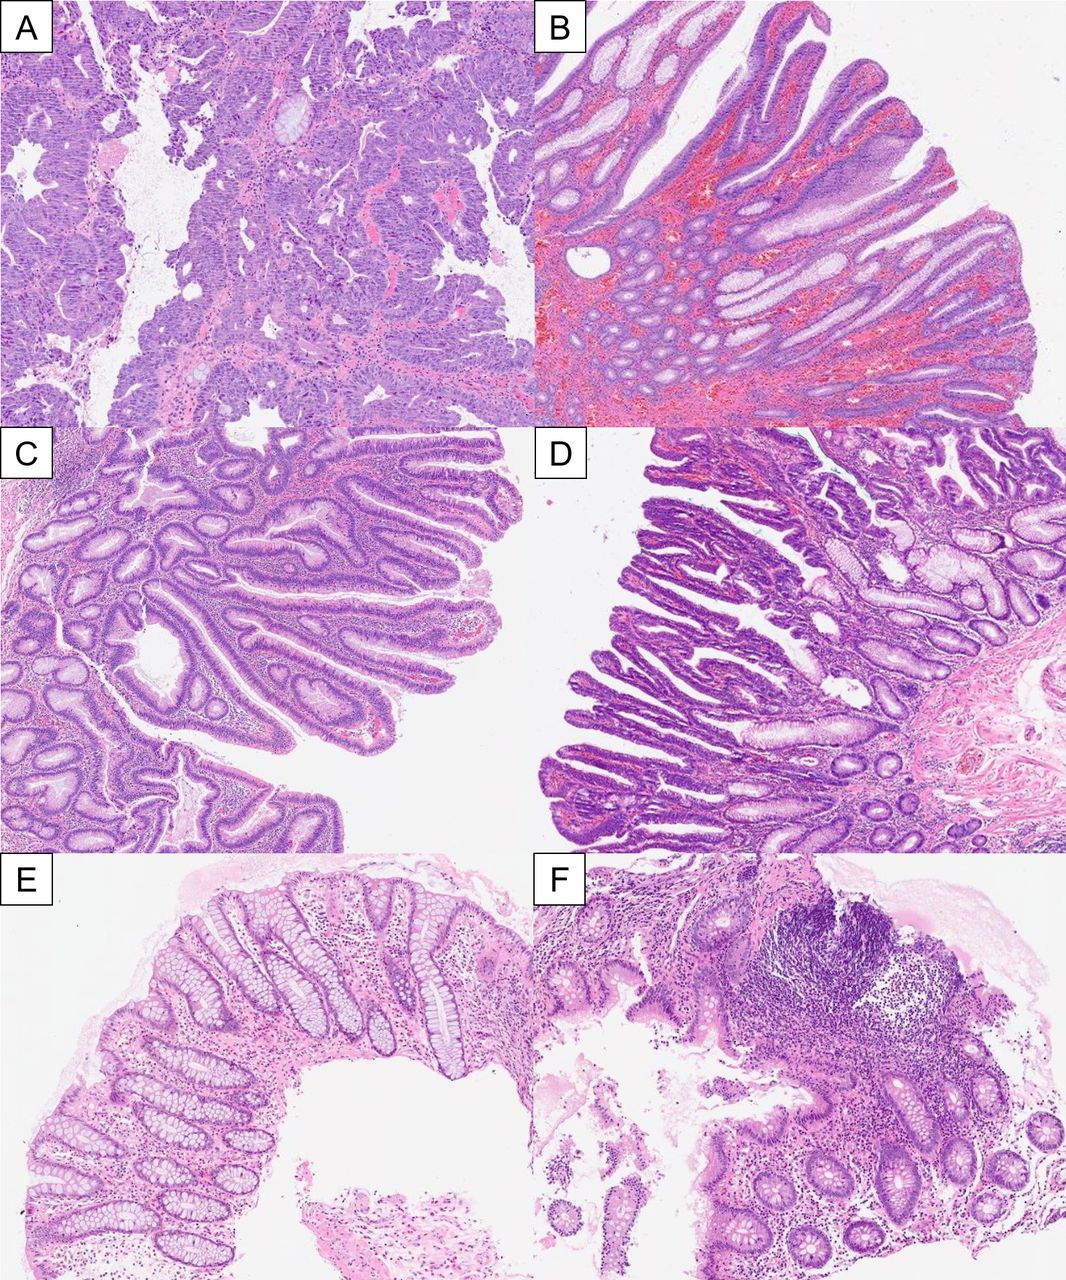

- Hyperplastic: Most common; colonic; serrated/sawtooth crypts on histology; usually no malignant potential.

- Peutz-Jeghers Polyps: Arborizing smooth muscle core. Syndrome (AD): mucocutaneous pigmentation, ↑ risk of GI & non-GI cancers (pancreas, breast, lung, ovary, testis). 📌 PJS: Pigmentation, Jejunum, Sex-cord tumors.

- Juvenile Polyposis: Cystically dilated glands, inflamed stroma. Syndrome (AD): ↑ colorectal cancer risk if multiple polyps (> extbf{5}).

- Tubular: Most common (~75%), pedunculated, lowest risk.

- Villous: Sessile, frond-like; highest malignant risk. 📌 Villainous Villous!

- Tubulovillous: Mix, intermediate risk.

- All show epithelial dysplasia (low/high grade).